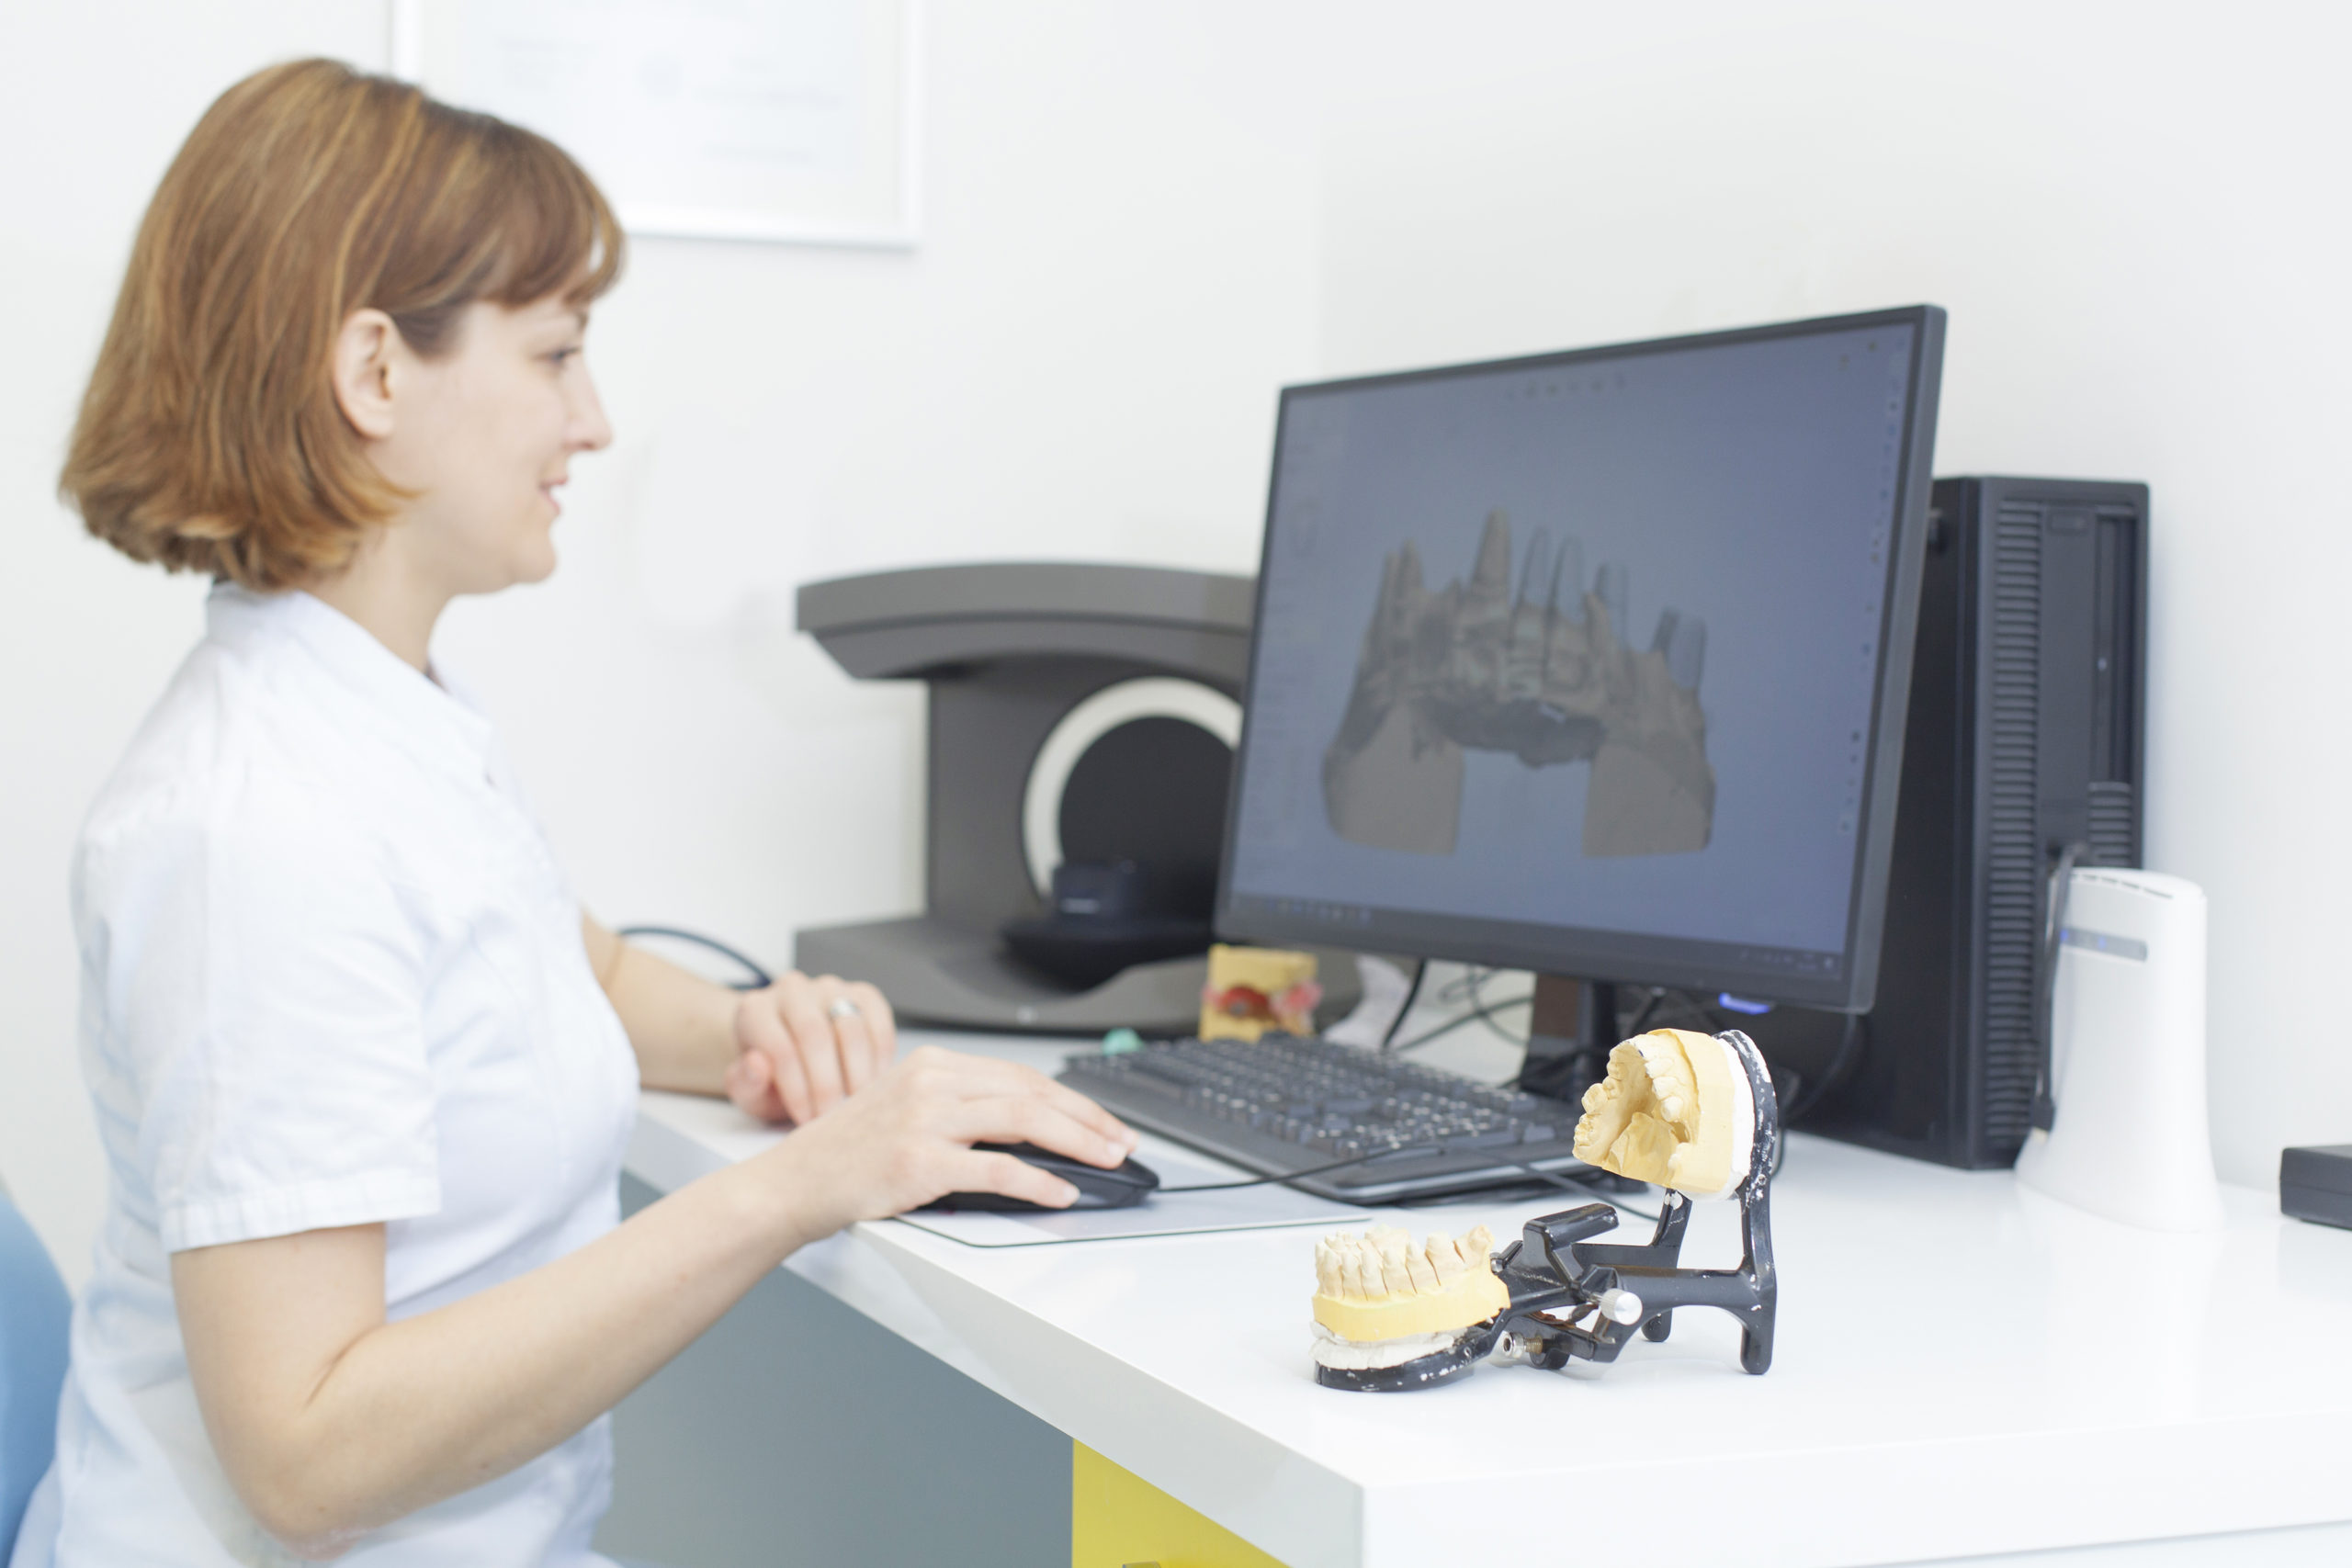

What Tools Are Best For Creating Digital Drawings Of Teeth And Smiles?

April 21, 2026Seeing your future smile before treatment begins is an incredible moment, not to mention a powerful motivator. It takes what was once an abstract plan and turns it into something […]